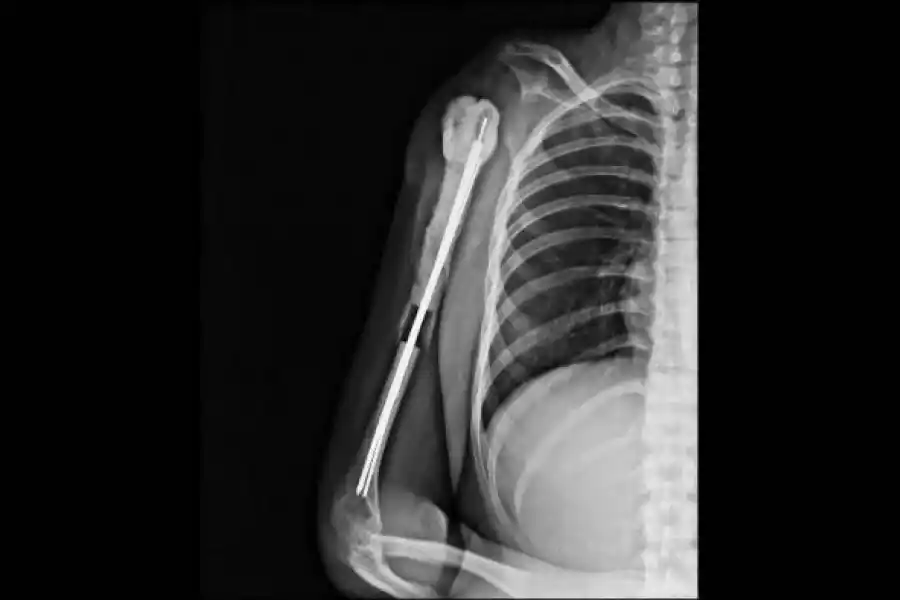

ANTES Y DESPUES. Las radiografías muestran cómo quedó el hombro de Andrea.